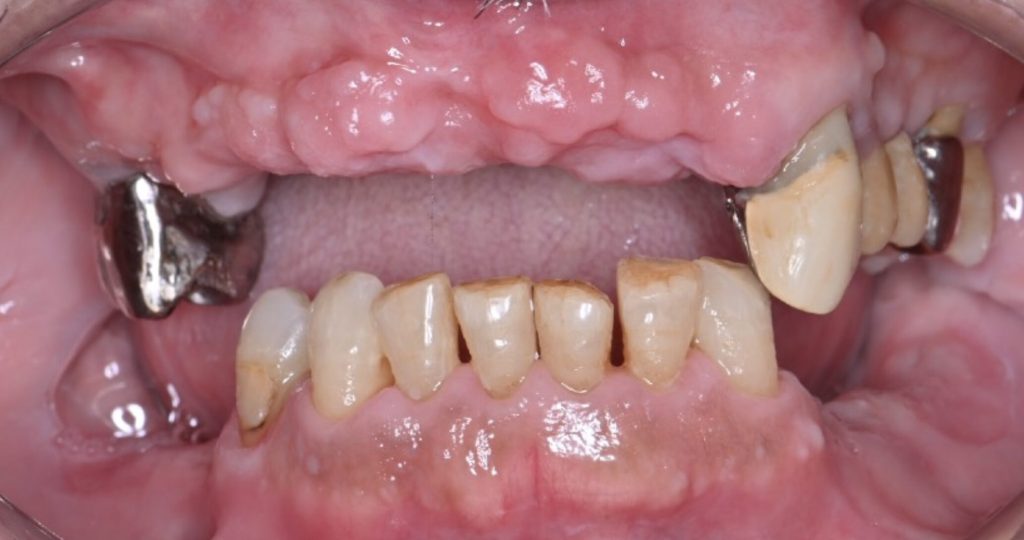

入れ歯では十分に噛めず、やわらかい炭水化物をたべてしまいがち。口の中のヌメヌメ、細菌性プラークの元です。

1930年代の報告では、肉中心の伝統的な食生活を送っていた北極圏のエスキモーの人々には、虫歯や歯周病がほとんど見られなかったとされています。一方で、コメや小麦などの炭水化物が食生活に加わることで、虫歯や歯周病のリスクが高まるという指摘もあります。こうしたことからも、噛めない状態が続くことで炭水化物の摂取が増え、残った歯の虫歯・歯周病がさらに悪化し歯が抜けていく悪循環に陥ることがわかります。